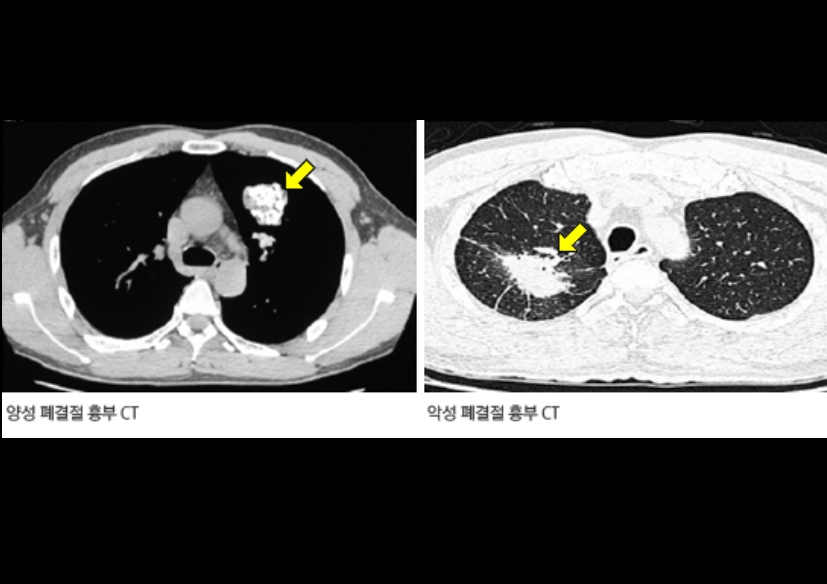

Q5. 흉부CT에서 종양이 발견되면 바로 조직검사를 하나요?

A. 꼭 그렇지는 않습니다. 결절이나 종양이 발견되더라도 크기, 모양, 경계, 주변 혈관과의 거리 등을 종합적으로 판단한 후 결정합니다. 크기가 작고 둥글며 경계가 뚜렷한 경우는 양성일 가능성이 높아 3~6개월 후 추적검사를 하기도 합니다. 그러나 비정상적인 모양이나 크기 변화가 빠른 경우에는 조직검사(생검)를 진행합니다.

Q8. 흉부CT 결과에서 ‘폐결절’이 나왔다는 말은 뭔가요?

A. 흉부ct로 볼수있는 질환 폐결절은 말 그대로 폐 안에 작은 혹이 있다는 뜻입니다. 대부분 양성(암이 아님)이고, 오래된 염증이나 석회화에 의한 것일 수도 있습니다. 그러나 결절의 크기가 8mm 이상이거나, 형태가 불규칙한 경우에는 추가 검사가 필요합니다. 영상의학과에서는 결절의 밀도, 경계, 주변 변화 등을 세밀하게 분석해 암 가능성을 판단합니다.